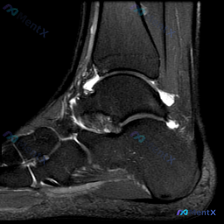

病例整理 今天看到一个很有警示意义的病例,整理给大家一起讨论 基本信息 - 年龄:23岁,女性 - 主诉:右膝疼痛无法跑步2天 病史 现病史:疼痛位于膝盖骨下方,评分5/10,久坐加重到8/10,从坐姿站起时偶尔有弹响感,无膝盖外伤史。 既往史:2年前右锁骨骨折,吊带保守治疗治愈。 个人史:不吸烟,...

刚看到一个有意思的临床病例,整理出来和大家聊聊,整体思路挺值得回味的。 病例基本信息 患者: 23岁女性,办公室工作 主诉: 右膝受伤后不能跑步,疼痛2天 现病史: 疼痛位于膝盖骨下方,评分5/10,久坐时加重到8/10,从坐姿站起时偶尔有弹响感,无膝盖外伤史 既往史: 2年前右锁骨骨折,吊带治疗治...